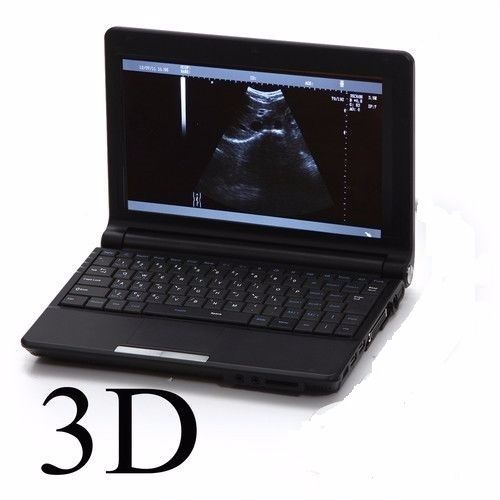

3D Ultrasound Capabilities

The integration of 3D imaging technology in the Laptop Ultrasound scanner transforms the diagnostic experience. This feature not only enhances image clarity but also provides a comprehensive view of anatomical structures, making diagnosis more reliable. Doctors can identify issues earlier and more accurately because they can see three-dimensional representations of organs. This capability is particularly important in prenatal care and gynecological assessments, ensuring better health outcomes for patients.